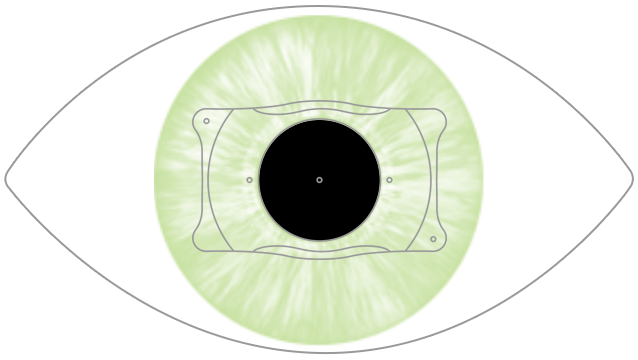

Product id: Lente intraocular on sale faquica

Lentes Intraoculares F quicas introducci n y complicaciones on sale, Iris Fixated Phakic Intraocular Lens Implantation on sale, Implantaci n de lentes intraoculares f quicos y f quicos t ricos on sale, Lentes intraoculares f quicas on sale, Lente intraocular f quico cirug a que permite dejar de usar on sale, Intraocular Lenses Incornea ENG on sale, Visian ICL lentes intraoculares f quicas on sale, Dr. Gonzalo Gallegos La implantaci n de lente intraocular on sale, Implantaci n de lentes intraoculares f quicos y f quicos t ricos on sale, Lentes F quicas oculares rea Oftalmol gica Avanzada on sale, Implante de Lentes Arbrayss L ser Oftalmolog a Pioneros en on sale, Lentes F quicas rea Oftalmol gica Avanzada Dr. Darchuk on sale, Lente Intraocular F quica ICL on sale, Precio Cirugia Intraocular Sale Online SAVE 51 factoria 4 7 on sale, Implante de lentes intraoculares todo lo que debes saber on sale, Correcci n de la alta miop a con implante de lente f quica ACR 128 on sale, Multimedia Dr. Luis Fernando Mej a Oftalm logo Medell n Colombia on sale, Lentes Intraoculares F quicas en Vista Mallorca Facorefractiva on sale, Lentes intraoculares f quicas ICL Cl nicas Tecnovision on sale, Lentes Intraoculares LIO T ricas Cl nica Oftalmol gica Santa on sale, Lente intraocular f quica de c mara anterior de fijaci n angular on sale, Miranza IOA LENTES F QUICAS ICL on sale, Qu son las Lentes F quicas rea Oftalmol gica Avanzada on sale, Lentes ICL o Lentes Intraoculares Ventajas e Indicaciones on sale, Lentes Intraoculares F quicas introducci n y complicaciones on sale, Las lentes intraoculares f quicas una soluci n en auge para on sale, Cirug a de Implante de Lente Intraocular F quico en Ibagu Tolima on sale, Implantaci n de lente intraocular de c mara anterior on sale, Multimedia Dr. Luis Fernando Mej a Oftalm logo Medell n Colombia on sale, Lente Intraocular F quico Curiel Visi n on sale, Lente F quica Dr. Fernando Mayorga on sale, Lente intraocular f quica fotograf as e im genes de alta on sale, Lentes intraoculares f quicas Wikipedia la enciclopedia libre on sale, Vista de Tecnolog as para la emetrop a Archivos Argentinos de on sale, Miop a hipermetrop a y astigmatismo Dr. Diego Croce on sale, Ceoval Centro Oftalmol gico de Valencia Sabes que la lente on sale, Cirug a de lente intraocular Dra. Elisa Nieto Torres on sale, Lentes intraoculares f quicas ICL IO ICO Barcelona on sale, Lente intraocular f quica fotograf as e im genes de alta on sale, Cirug a de catarata explante lente f quica PRL on sale, C mo se coloca el lente intraocular f quico Conoce todos los detalles on sale, Implante de Lente Intraocular Dr Gabriel Oliveros on sale, LENTE INTRAOCULAR Faquico Fijaci n En el Iris ppt descargar on sale, Lentes F quicas Cirurgia para miopia lentes intra oculares on sale, Cirug a de lente f quica Intraocular ICL Smart Laser Eye Center on sale, Dra. Paola Zurita Ferrel Cirujana Oftalm loga Qu son las on sale, Lentes F cicas Altas Ametropias on sale, Lente Faquico Torico en Paciente con Queratocono Operado de Anillos Intraestromales on sale, Cirug as de cambio de color de ojos e implantes de iris on sale, Lente intraocular f quica de c mara anterior de fijaci n angular on sale.

Lentes Intraoculares F quicas introducci n y complicaciones on sale, Iris Fixated Phakic Intraocular Lens Implantation on sale, Implantaci n de lentes intraoculares f quicos y f quicos t ricos on sale, Lentes intraoculares f quicas on sale, Lente intraocular f quico cirug a que permite dejar de usar on sale, Intraocular Lenses Incornea ENG on sale, Visian ICL lentes intraoculares f quicas on sale, Dr. Gonzalo Gallegos La implantaci n de lente intraocular on sale, Implantaci n de lentes intraoculares f quicos y f quicos t ricos on sale, Lentes F quicas oculares rea Oftalmol gica Avanzada on sale, Implante de Lentes Arbrayss L ser Oftalmolog a Pioneros en on sale, Lentes F quicas rea Oftalmol gica Avanzada Dr. Darchuk on sale, Lente Intraocular F quica ICL on sale, Precio Cirugia Intraocular Sale Online SAVE 51 factoria 4 7 on sale, Implante de lentes intraoculares todo lo que debes saber on sale, Correcci n de la alta miop a con implante de lente f quica ACR 128 on sale, Multimedia Dr. Luis Fernando Mej a Oftalm logo Medell n Colombia on sale, Lentes Intraoculares F quicas en Vista Mallorca Facorefractiva on sale, Lentes intraoculares f quicas ICL Cl nicas Tecnovision on sale, Lentes Intraoculares LIO T ricas Cl nica Oftalmol gica Santa on sale, Lente intraocular f quica de c mara anterior de fijaci n angular on sale, Miranza IOA LENTES F QUICAS ICL on sale, Qu son las Lentes F quicas rea Oftalmol gica Avanzada on sale, Lentes ICL o Lentes Intraoculares Ventajas e Indicaciones on sale, Lentes Intraoculares F quicas introducci n y complicaciones on sale, Las lentes intraoculares f quicas una soluci n en auge para on sale, Cirug a de Implante de Lente Intraocular F quico en Ibagu Tolima on sale, Implantaci n de lente intraocular de c mara anterior on sale, Multimedia Dr. Luis Fernando Mej a Oftalm logo Medell n Colombia on sale, Lente Intraocular F quico Curiel Visi n on sale, Lente F quica Dr. Fernando Mayorga on sale, Lente intraocular f quica fotograf as e im genes de alta on sale, Lentes intraoculares f quicas Wikipedia la enciclopedia libre on sale, Vista de Tecnolog as para la emetrop a Archivos Argentinos de on sale, Miop a hipermetrop a y astigmatismo Dr. Diego Croce on sale, Ceoval Centro Oftalmol gico de Valencia Sabes que la lente on sale, Cirug a de lente intraocular Dra. Elisa Nieto Torres on sale, Lentes intraoculares f quicas ICL IO ICO Barcelona on sale, Lente intraocular f quica fotograf as e im genes de alta on sale, Cirug a de catarata explante lente f quica PRL on sale, C mo se coloca el lente intraocular f quico Conoce todos los detalles on sale, Implante de Lente Intraocular Dr Gabriel Oliveros on sale, LENTE INTRAOCULAR Faquico Fijaci n En el Iris ppt descargar on sale, Lentes F quicas Cirurgia para miopia lentes intra oculares on sale, Cirug a de lente f quica Intraocular ICL Smart Laser Eye Center on sale, Dra. Paola Zurita Ferrel Cirujana Oftalm loga Qu son las on sale, Lentes F cicas Altas Ametropias on sale, Lente Faquico Torico en Paciente con Queratocono Operado de Anillos Intraestromales on sale, Cirug as de cambio de color de ojos e implantes de iris on sale, Lente intraocular f quica de c mara anterior de fijaci n angular on sale.